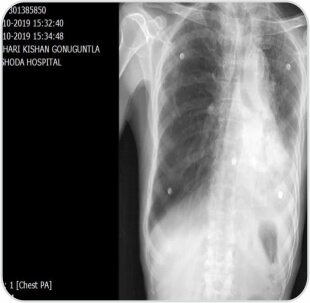

Post procedure radiograph showingaerated left lung